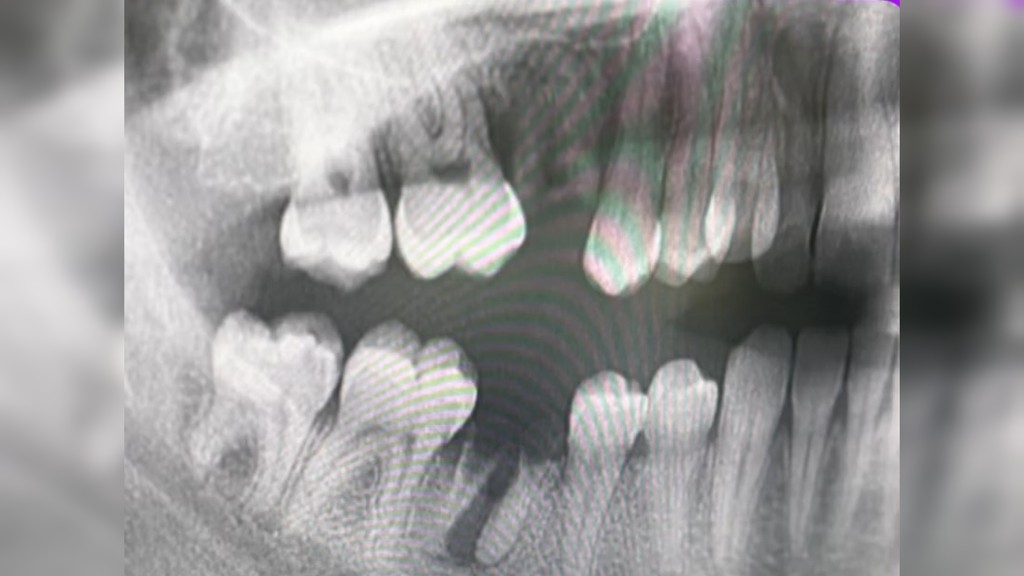

Snímka ústnej dutiny pacienta Zdroj: Instagram/nat_hygiena

U daného pacienta zápal z koreňového systému postihnutého zuba postupne prestúpil do okolitého tkaniva a vytvoril absces, ktorý si napokon prerazil cestu smerom von cez mäkké tkanivo líca.

„Takýto priebeh je síce zriedkavý, no žiaľ, nie nemožný. O to viac podčiarkuje, aké dôležité je nepodceňovať ani ‚len‘ kaz,“ doplnila hygienička.

„Neviem si ani len predstaviť, ako tento proces abscesu a rozpúšťania kosti musel bolieť,“ poznamenala s tým, že pacient sa bál prísť.